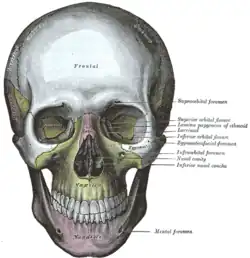

Vista lateral do crânio. Crânio visto de frente.

Crânio visto de frente. Close-up.